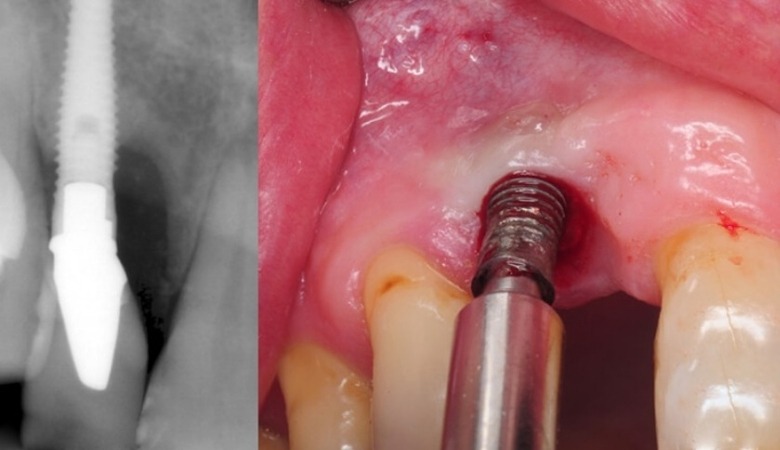

Một trong những rủi ro hàng đầu khi trồng răng implant giá rẻ là nguy cơ nhiễm trùng vết thương sau phẫu thuật. Các phòng khám nha khoa không uy tín thường không đảm bảo được điều kiện vô trùng tuyệt đối trong quá trình thực hiện. Việc sử dụng các thiết bị y tế không được khử khuẩn đúng cách, môi trường phẫu thuật không đạt chuẩn có thể tạo điều kiện thuận lợi cho vi khuẩn xâm nhập vào vết thương.

Trụ implant giá rẻ thường được làm từ vật liệu không đảm bảo chất lượng, có thể lẫn tạp chất. Những tạp chất này không chỉ làm tăng nguy cơ kích ứng mà còn tạo môi trường lý tưởng cho vi khuẩn phát triển, dẫn đến tình trạng viêm nhiễm kéo dài. Nhiễm trùng vùng cấy implant có thể gây ra các triệu chứng như sưng đau, chảy mủ, thậm chí là sốt, ảnh hưởng nghiêm trọng đến quá trình tích hợp xương của trụ implant và sức khỏe tổng thể.

Trụ implant bị đào thải

Quá trình tích hợp xương là yếu tố then chốt quyết định sự thành công của ca cấy ghép implant. Trụ implant cần phải tích hợp chắc chắn vào xương hàm để có thể nâng đỡ mão răng sứ và chịu được lực ăn nhai. Tuy nhiên, khi lựa chọn trồng răng implant giá rẻ, nguy cơ trụ implant bị đào thải là rất cao.

Nguyên nhân chính dẫn đến tình trạng này thường xuất phát từ chất lượng trụ implant kém. Các loại trụ giá rẻ thường không được làm từ titanium nguyên chất hoặc có bề mặt xử lý không tốt, làm giảm khả năng tương thích sinh học với xương hàm. Bên cạnh đó, tay nghề bác sĩ thực hiện cũng đóng vai trò quan trọng. Bác sĩ thiếu kinh nghiệm, thực hiện sai kỹ thuật có thể đặt trụ implant không đúng vị trí, không đảm bảo độ ổn định ban đầu, dẫn đến việc trụ không thể tích hợp với xương và bị đào thải theo thời gian.